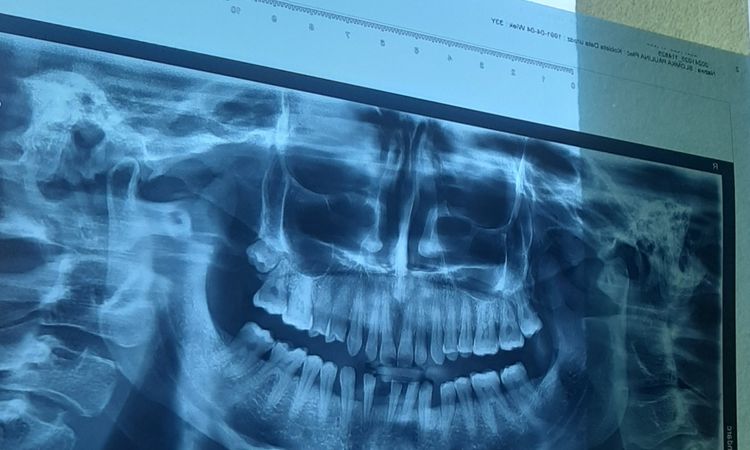

Wstawienie korony cyrkonowej na 6 zebach

Witam . Jaki jest koszt korony cyrkonowej na 6 zebach na dolnej szczece z brakującym jednym zębem. Dołączam zdjęcie.